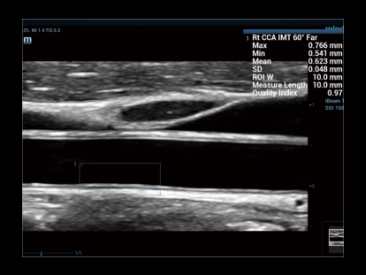

?valuation intelligente de la stûˋatose hûˋpatique par le calcul automatique de la luminositûˋ hûˋpatique avec le cortex rûˋnal en mode?B.